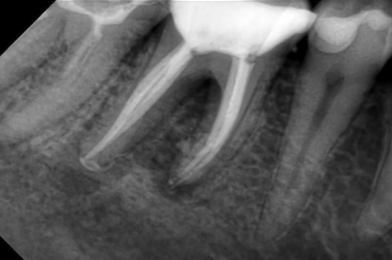

Extinderea tratamentului endodontic la nivelul întregii anatomii este mai sigură în cazul folosirii microscopului operator. În această situație, acestui molar inferior i-au fost tratate 3 canale, așa cum este forma anatomică (Fig. 4.12.1). Doar că în această situație sistemul endodontic prezenta 6 canale, toate instrumentate și obturate cu ocazia retratamentului. (Fig. 4.12.2, Fig. 4.12.3)

În acest caz, pacientul s-a prezentat după un abces acut în antecedente (durere puternică și spontană, cu caracter pulsatil) care a fost tratat cu antibiotice. La analiza imagisticii 3D remarcăm că există o comunicare între materialul din interiorul dintelui și spațiul dintre cele două rădăcini. Se mai evidențiază și material extrudat în acest spațiu, precum și pierdere osoasă. Deducem că este vorba de pierdere osoasă în furcație în urma cimentării unui pivot turnat. Acest pivot a fost cimentat într-un spațiu artificial creat în afara rădăcinii, această acțiune fiind un accident al tratamentului inițial (Fig. 4.12.4). Prima măsură este de a asigura izolarea cu diga dentară. Dintele prezintă o coroană artificială ce trebuie îndepărtată, diga ferește pacientul de contactul cu pulberile rezultate în urma tăierii coroanei (Fig. 4.12.5).